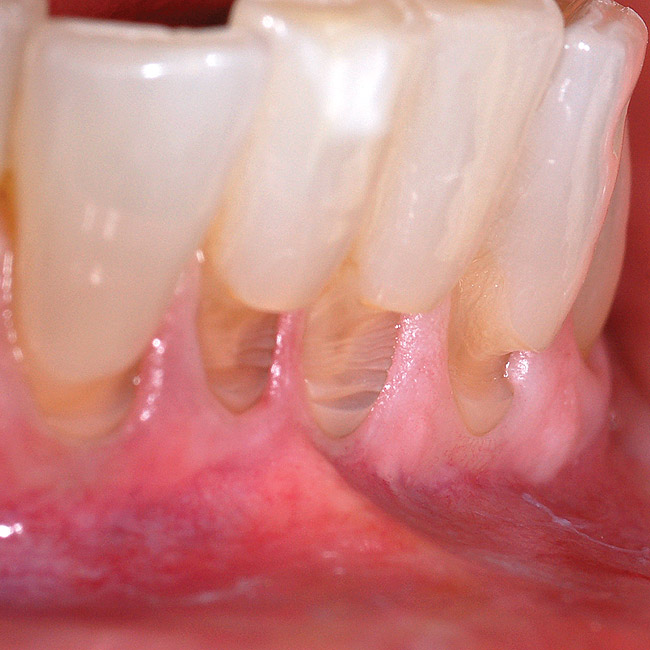

Fig 1 and Fig 2. Non-carious cervical lesion on the root surface of a maxillary canine. There was no attached gingiva, the cervical lesion was less than 2 mm in depth, and the recession was Miller Class I.